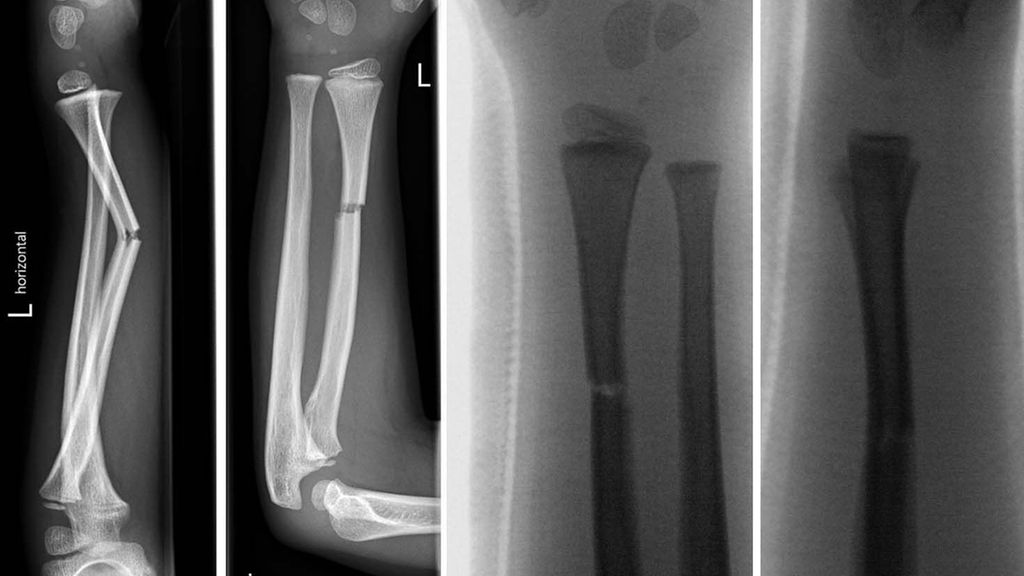

Abb. 9: Fallbeispiel: 6-jähriger Patient mit Radiusschaftfraktur. Unfall (a, b); Reposition (c, d); Stellungskontrolle mit sekundärer Achsabweichung Tag 9 (e, f); Stellungskontrolle 6 Tage nach Keilung (g, h)